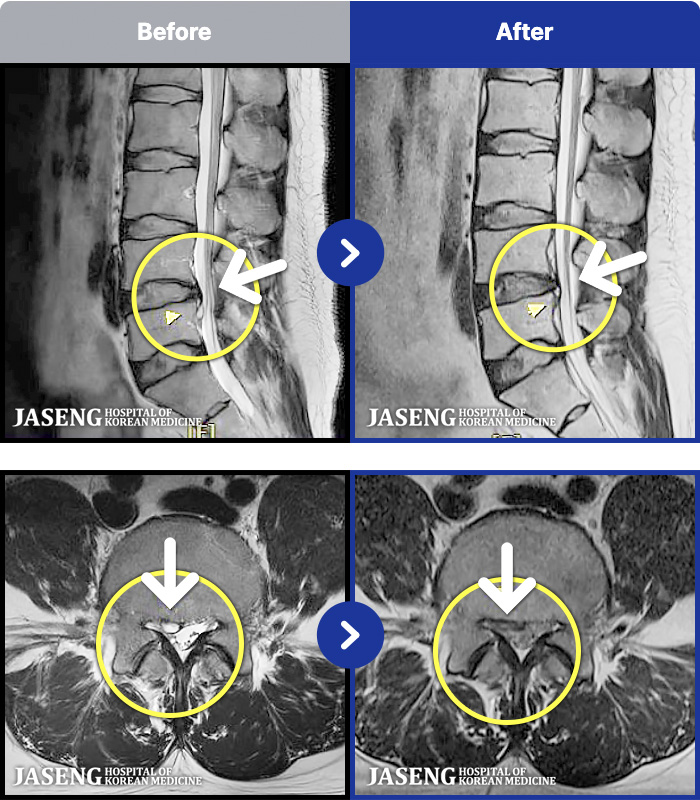

1,297 MRI ũ ʸ Ȯϼ.

[] 23.11.11~25.06.04